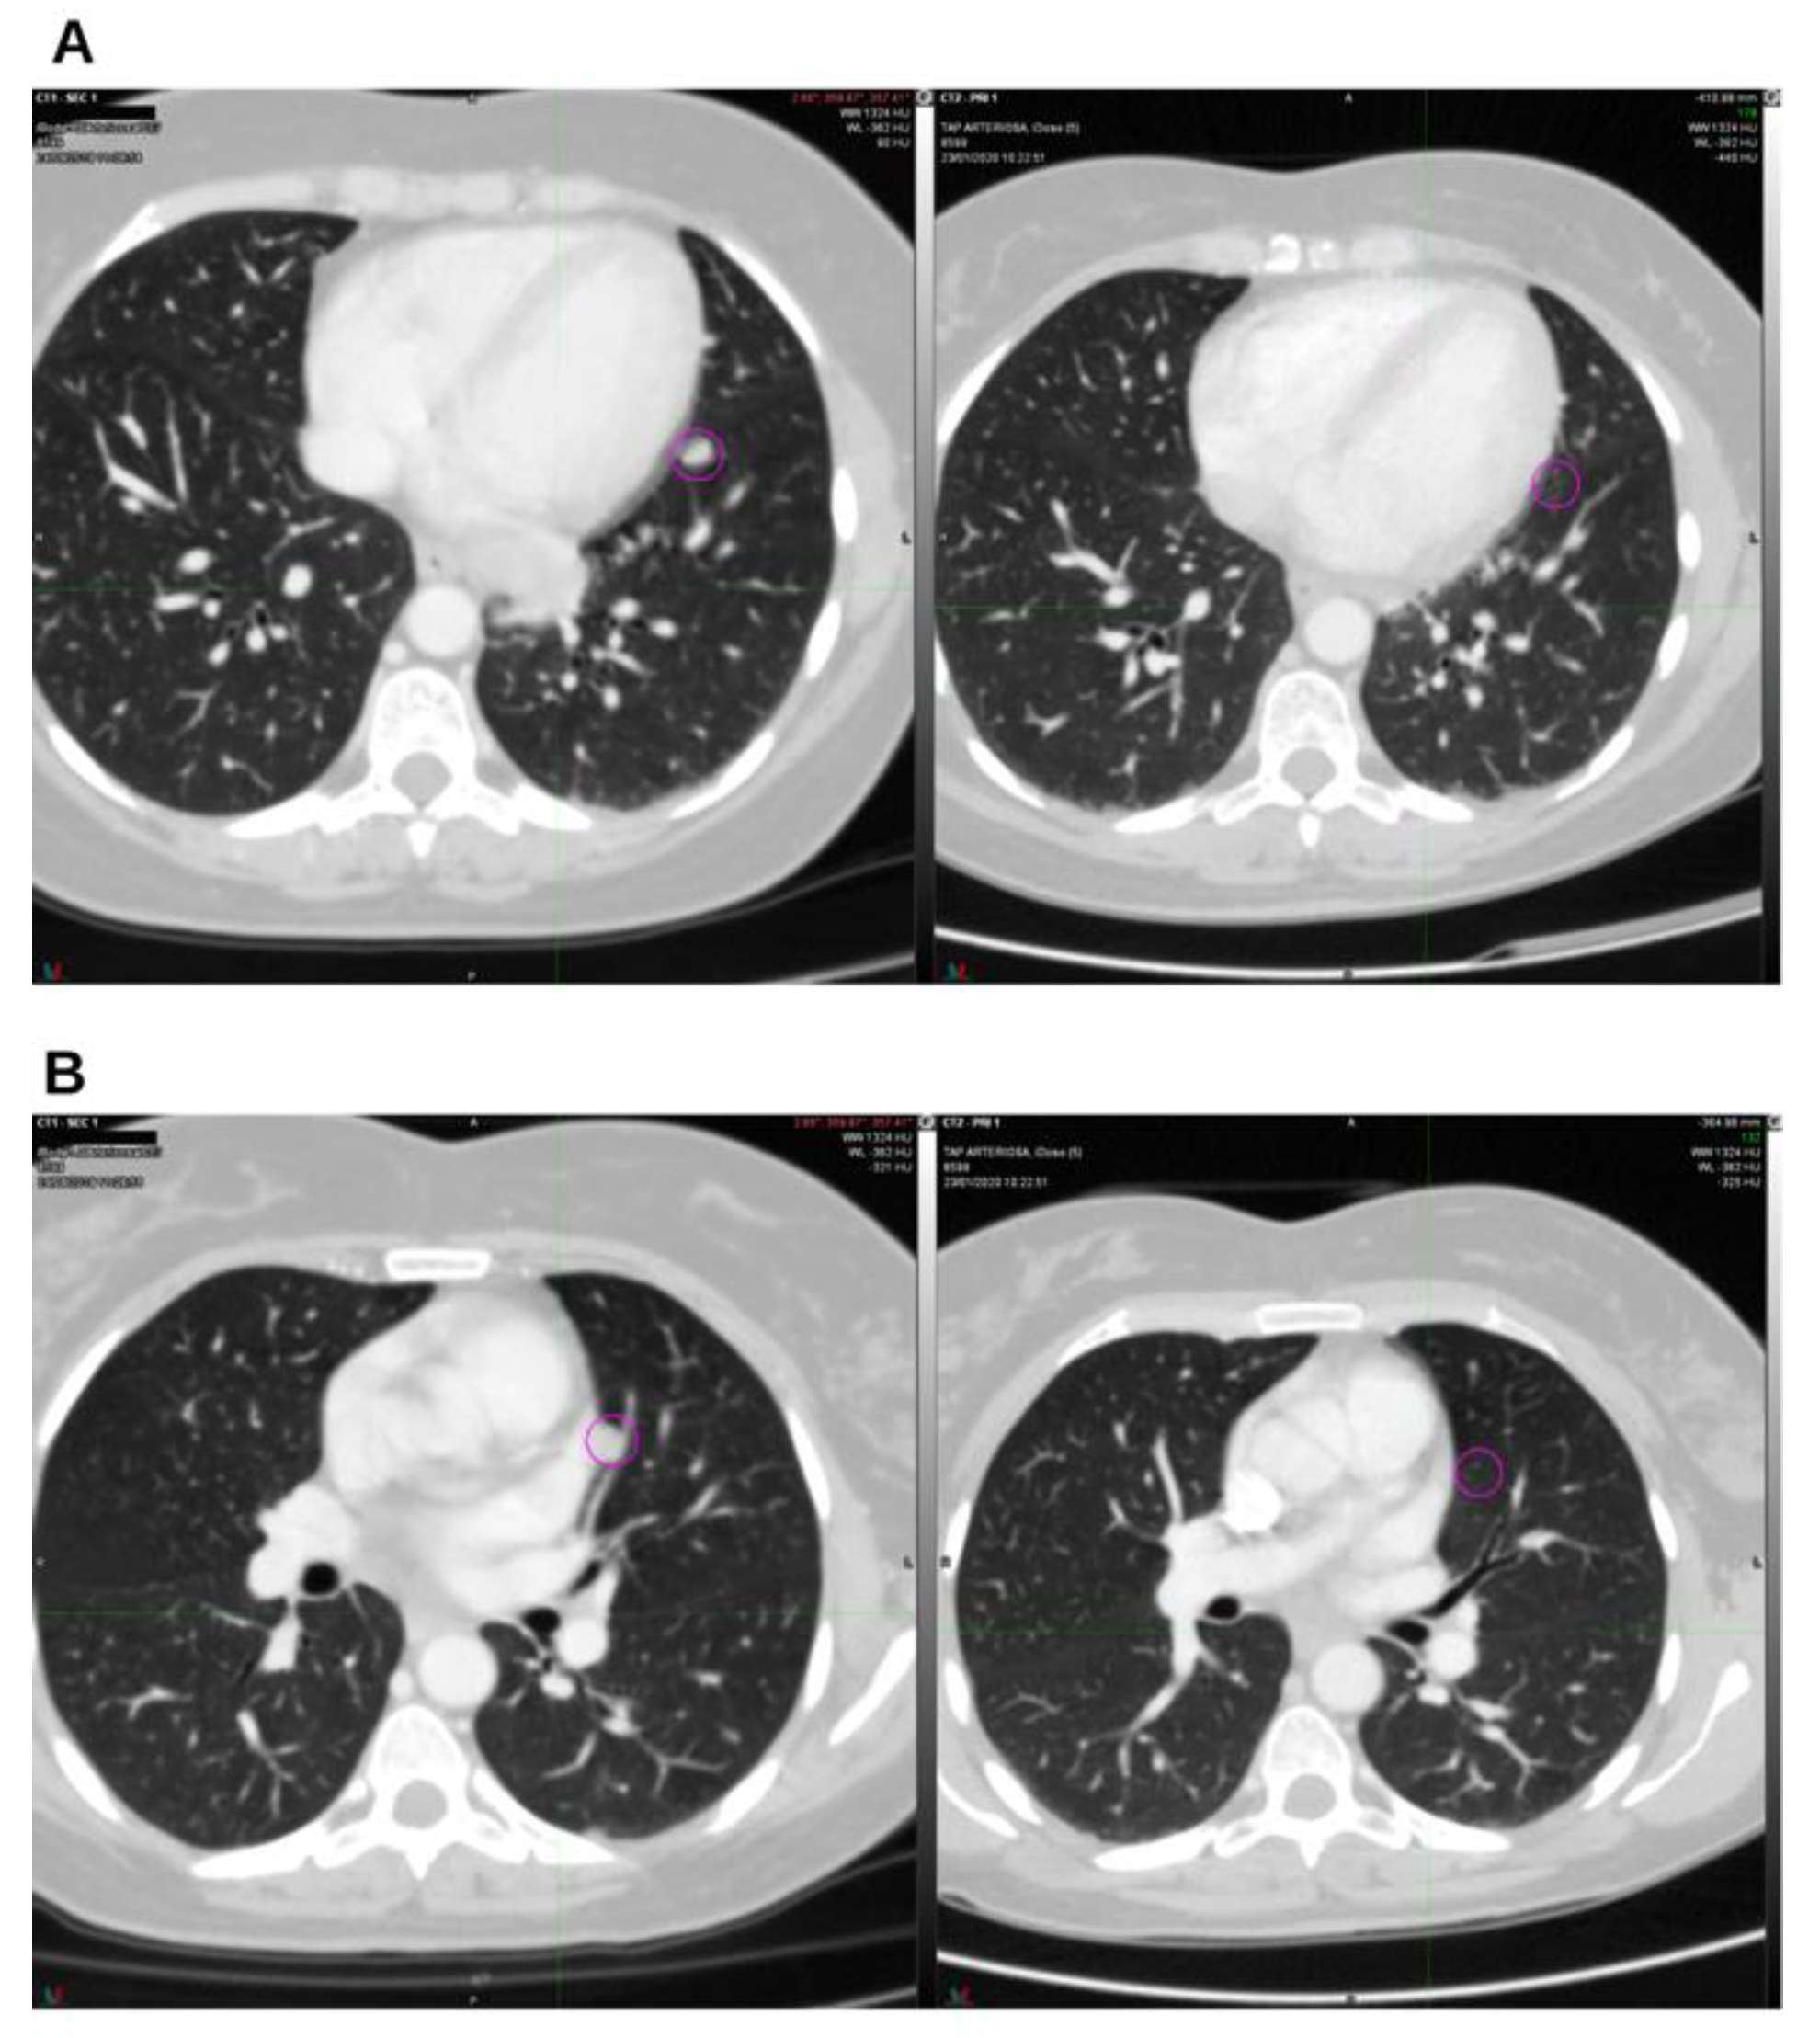

Background and Clinical Significance: Breast cancer is the most frequent malignancy in women. Advanced metastatic breast cancer is considered a treatable but incurable condition, with a median overall survival of only 2-3 years. Among its subtypes, triple-negative breast cancer (TNBC) accounts for a high proportion of breast cancer–related deaths. It is characterized by an aggressive clinical course, early recurrence, and a strong propensity for visceral and brain metastases. Case Presentation :We report the case of a Caucasian woman who, two years after being initially diagnosed and treated for TNBC, developed disease relapse with lung and mediastinal lymph node metastases. The patient received three months of chemotherapy combined with an adjuvant integrative protocol consisting of melatonin, cannabidiol, and oxygen–ozone therapy. This combined approach led to the complete disappearance of the lung nodules. Subsequently, stereotactic radiotherapy was performed and, in association with the ongoing integrative treatment, resulted in a significant reduction of mediastinal adenopathy. Introduction of immunotherapy, supported continuously by the same adjuvant strategy, achieved a complete and durable remission. Strikingly, the patient remained disease-free five years after the diagnosis of lung and mediastinal metastases. Conclusions: This clinical case highlights the potential benefit of using melatonin, cannabidiol, and oxygen–ozone therapy as part of an integrative approach in patients with aggressive metastatic TNBC. While it is not possible to establish causality from a single case, the sustained remission observed suggests that such unconventional adjuvant strategies could play a supportive role in enhancing the efficacy of standard oncologic therapies.